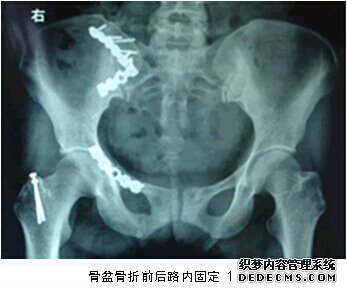

二、創傷學組:我科在四肢常見骨折的治療方面積累了豐富的臨床經驗。成功開展了微創小切口下人工髖關節置換術,有限內固定結合外固定支架治療復雜的開放性骨折,前后路固定復雜的骨盆骨折等新的業務,取得了良好的社會及經濟效益。

2、對各類骨折創傷療效顯著,患肢功能恢復佳:特別是高齡股骨頸、轉子間骨折患者行人工關節置換治療;高齡轉子間骨折患者行PFN/PFNA治療;對嚴重暴力所致的復雜性骨盆骨折行髖臼重建+外固定架治療;對于股骨髁上粉碎性骨折行關節面重建+鎖定鈦板內固定治療;對于脛骨平臺骨折內固定聯合關節鏡下關節面復位治療;嚴重踝關節骨折如pillion骨折行內外側鈦板固定聯合關節鏡下關節面復位;對于開放性骨折行多平面外固定架及Ilizarov環形架治療;部分肢體毀損傷及骨、皮膚缺損行血管神經吻合及各種皮瓣修復治療;